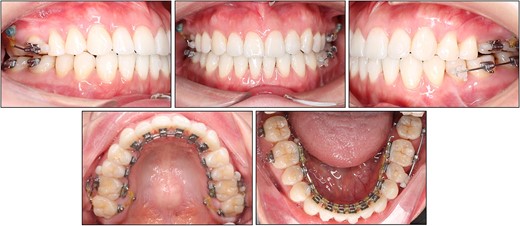

On intraoral evaluation, the patient had full-cusp class II molar and canine relationships on the right side and end-on class II molar and canine relationships on the left side. The anterior teeth and first premolars were in an open bite with an overbite of −3.1 mm. There was mild crowding of 1.2 mm in both arches. The upper dental midline was found to be deviated 1 mm to the left.

On a lateral cephalometric evaluation, the patient had a skeletal class I relationship (point A-nasion-point B angle, 4.0°) with a hyperdivergent facial pattern (Frankfort mandibular angle, 32.5°) (Table 1). The panoramic radiograph showed the presence of all teeth including the third molars (Fig. 2). The patient was diagnosed with an iatrogenic open bite and class II malocclusion on a skeletal class I relationship.